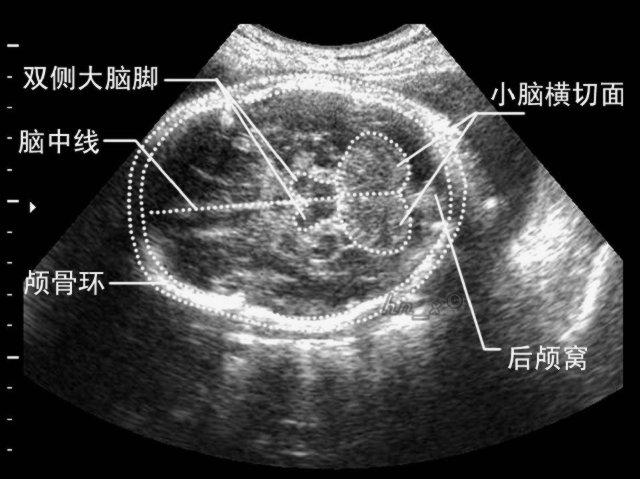

通过松果体,丘脑枕的尾部,上丘,脑干被盖,小脑中脚平面的冠状位